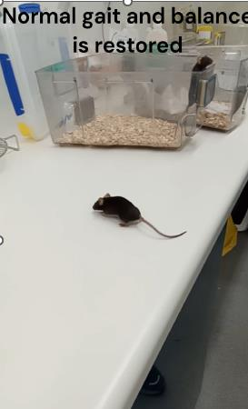

Mouse model shows remarkable improvement after treatment with DioprotectomeTM for 15 days

Day 15: The mouse exhibits MS symptoms (tail and hind limb paralysis) and was unable to walk properly

Full video is available in data room or can be accessed by scanning the QR code

Day 30 during the MS-like disease course (15 days after daily oral treatment with DioprotectomeTM): The mouse’s tail and hind-limb functions were restored and showed significant improvement in walking